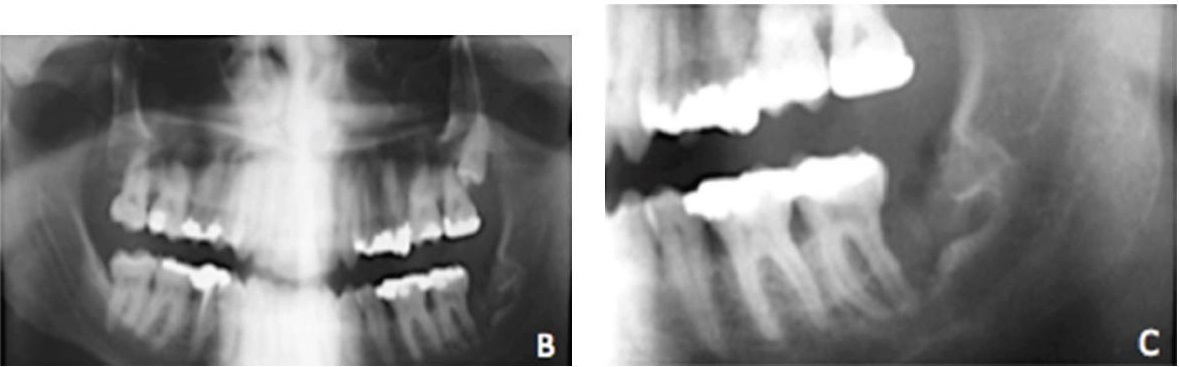

Есть шанс выявить заболевание во время рентгеновского обследования по поводу другой стоматологической проблемы. В этом случае, при допустимых размерах полости (в пределах одного сантиметра) можно применить терапевтическое лечение кисты зуба. При позднем обнаружении проблемы, чаще всего, приходится прибегать к хирургическим способам лечения. Они затрагивают целостность челюстной кости, а в некоторых ситуациях даже удаляется часть зуба.

После освобождения кистозной полости от гнойного содержимого ее заполняют специальным препаратом для повышения регенерации тканей. При терапевтическом лечении кисты зуба сначала ставится временная пломба. Для контроля эффективности пациент должен через шесть месяцев пройти на рентгенографию. Если результат удовлетворительный, корневой канал пломбируют и восстанавливают коронку. Но иногда после терапевтического лечения зуба случаются рецидивы. Поэтому важно регулярно посещать стоматолога для осмотра.